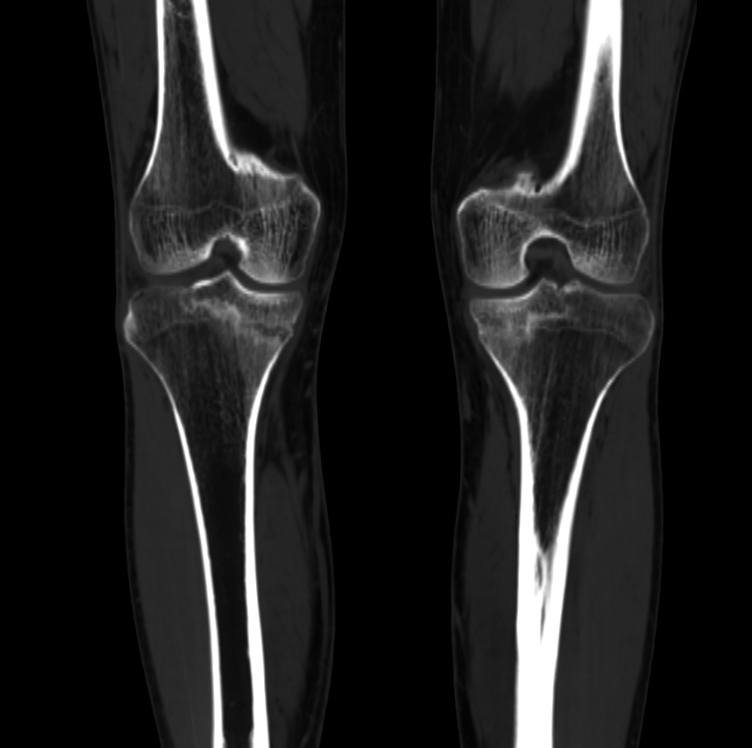

Тот случай, когда на рентгене видно то же, что и на КТ.

Переломы от перегрузки (маршевые, или, как сейчас модно говорить, стрессовые).

Военный, 30 лет.

Видали такое с обеих сторон?